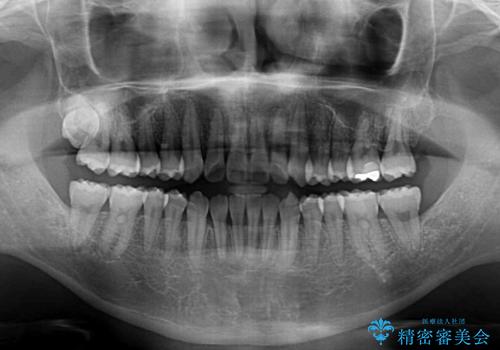

インビザラインによる反対咬合の改善は、上の歯が下の歯を乗り越えていく期間に咬み合わせが非常に不安定となり、治療が長期化することがあります。

また、ワイヤー矯正と異なり歯軸改善の強い力を前歯にかけるため、反対咬合で裏側にある歯の歯肉が退縮しやすくなります。

矯正治療により元々気になっていた八重歯と、反対咬合が改善された歯の2本に対して根面被覆を行い、審美面の改善も達成しました。